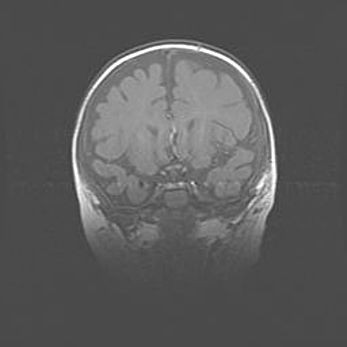

Открытая гидроцефалия.

Возраст: 9 месяцев 12 дней

Вес: 6800 г

Пол: мужской

Окружность головы: 41,5 см

Срок гестации: 28 недель

Гидроцефалия головного мозга у новорожденных имеет характерный признак: опережающий рост окружности головы приводит к визуально хорошо определяемой гидроцефальной форме сильно увеличенного в объёме черепа. Детские неврологи определяют следующие симптомы гидроцефалии у грудничков: выбухающий напряжённый родничок, частое запрокидывание головы, смещение глазных яблок к низу.